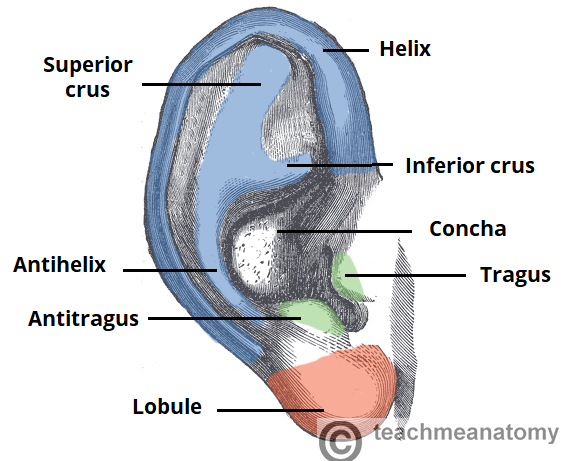

In the middle ear, how are sound waves transmitted into mechanical waves?

Vibration of ossicles

What are the ossicles? Names?

3 bones of the middle ear are the auditory ossicles that link the tympanic membrane to the oval window of the internal ear.

- Malleus (most lateral)

- Incus

- Stapes (most medial)

What are the smallest bones in the body?

Ossicles

What is the middle ear? Location?

Air filled space in the petrous part of the temporal bone

What separates the middle from the external ear?

Tympanic membrane

Which ossicle is in contact with the middle ear?

Stapes

Function of the ossicles?

- Vibrate to transmit/amplify sound waves into cochlea ear

- Bones vibrate to amplify sound

Ossicles can can calcify with age, becoming less flexible and less able to vibrate. What can this cause?

This can cause conductive hearing loss. May be progressive or complete.